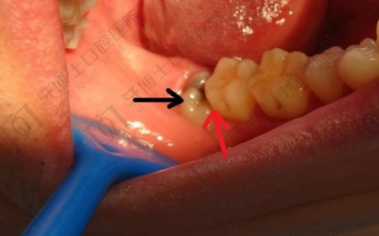

2、影响相邻牙齿的生长,通常因为空间不足,倒在第二磨牙上生长,第二磨牙不易清洁,易引起疼痛,最好拔除。

3、空间不足,因为人类在进化的过程中吃的食物越来越细,导致颌骨骨量减少,使得尽头牙没有足够的空间生长,此时尽头牙萌出易阻生,长歪,影响邻牙生长,最好拔除。